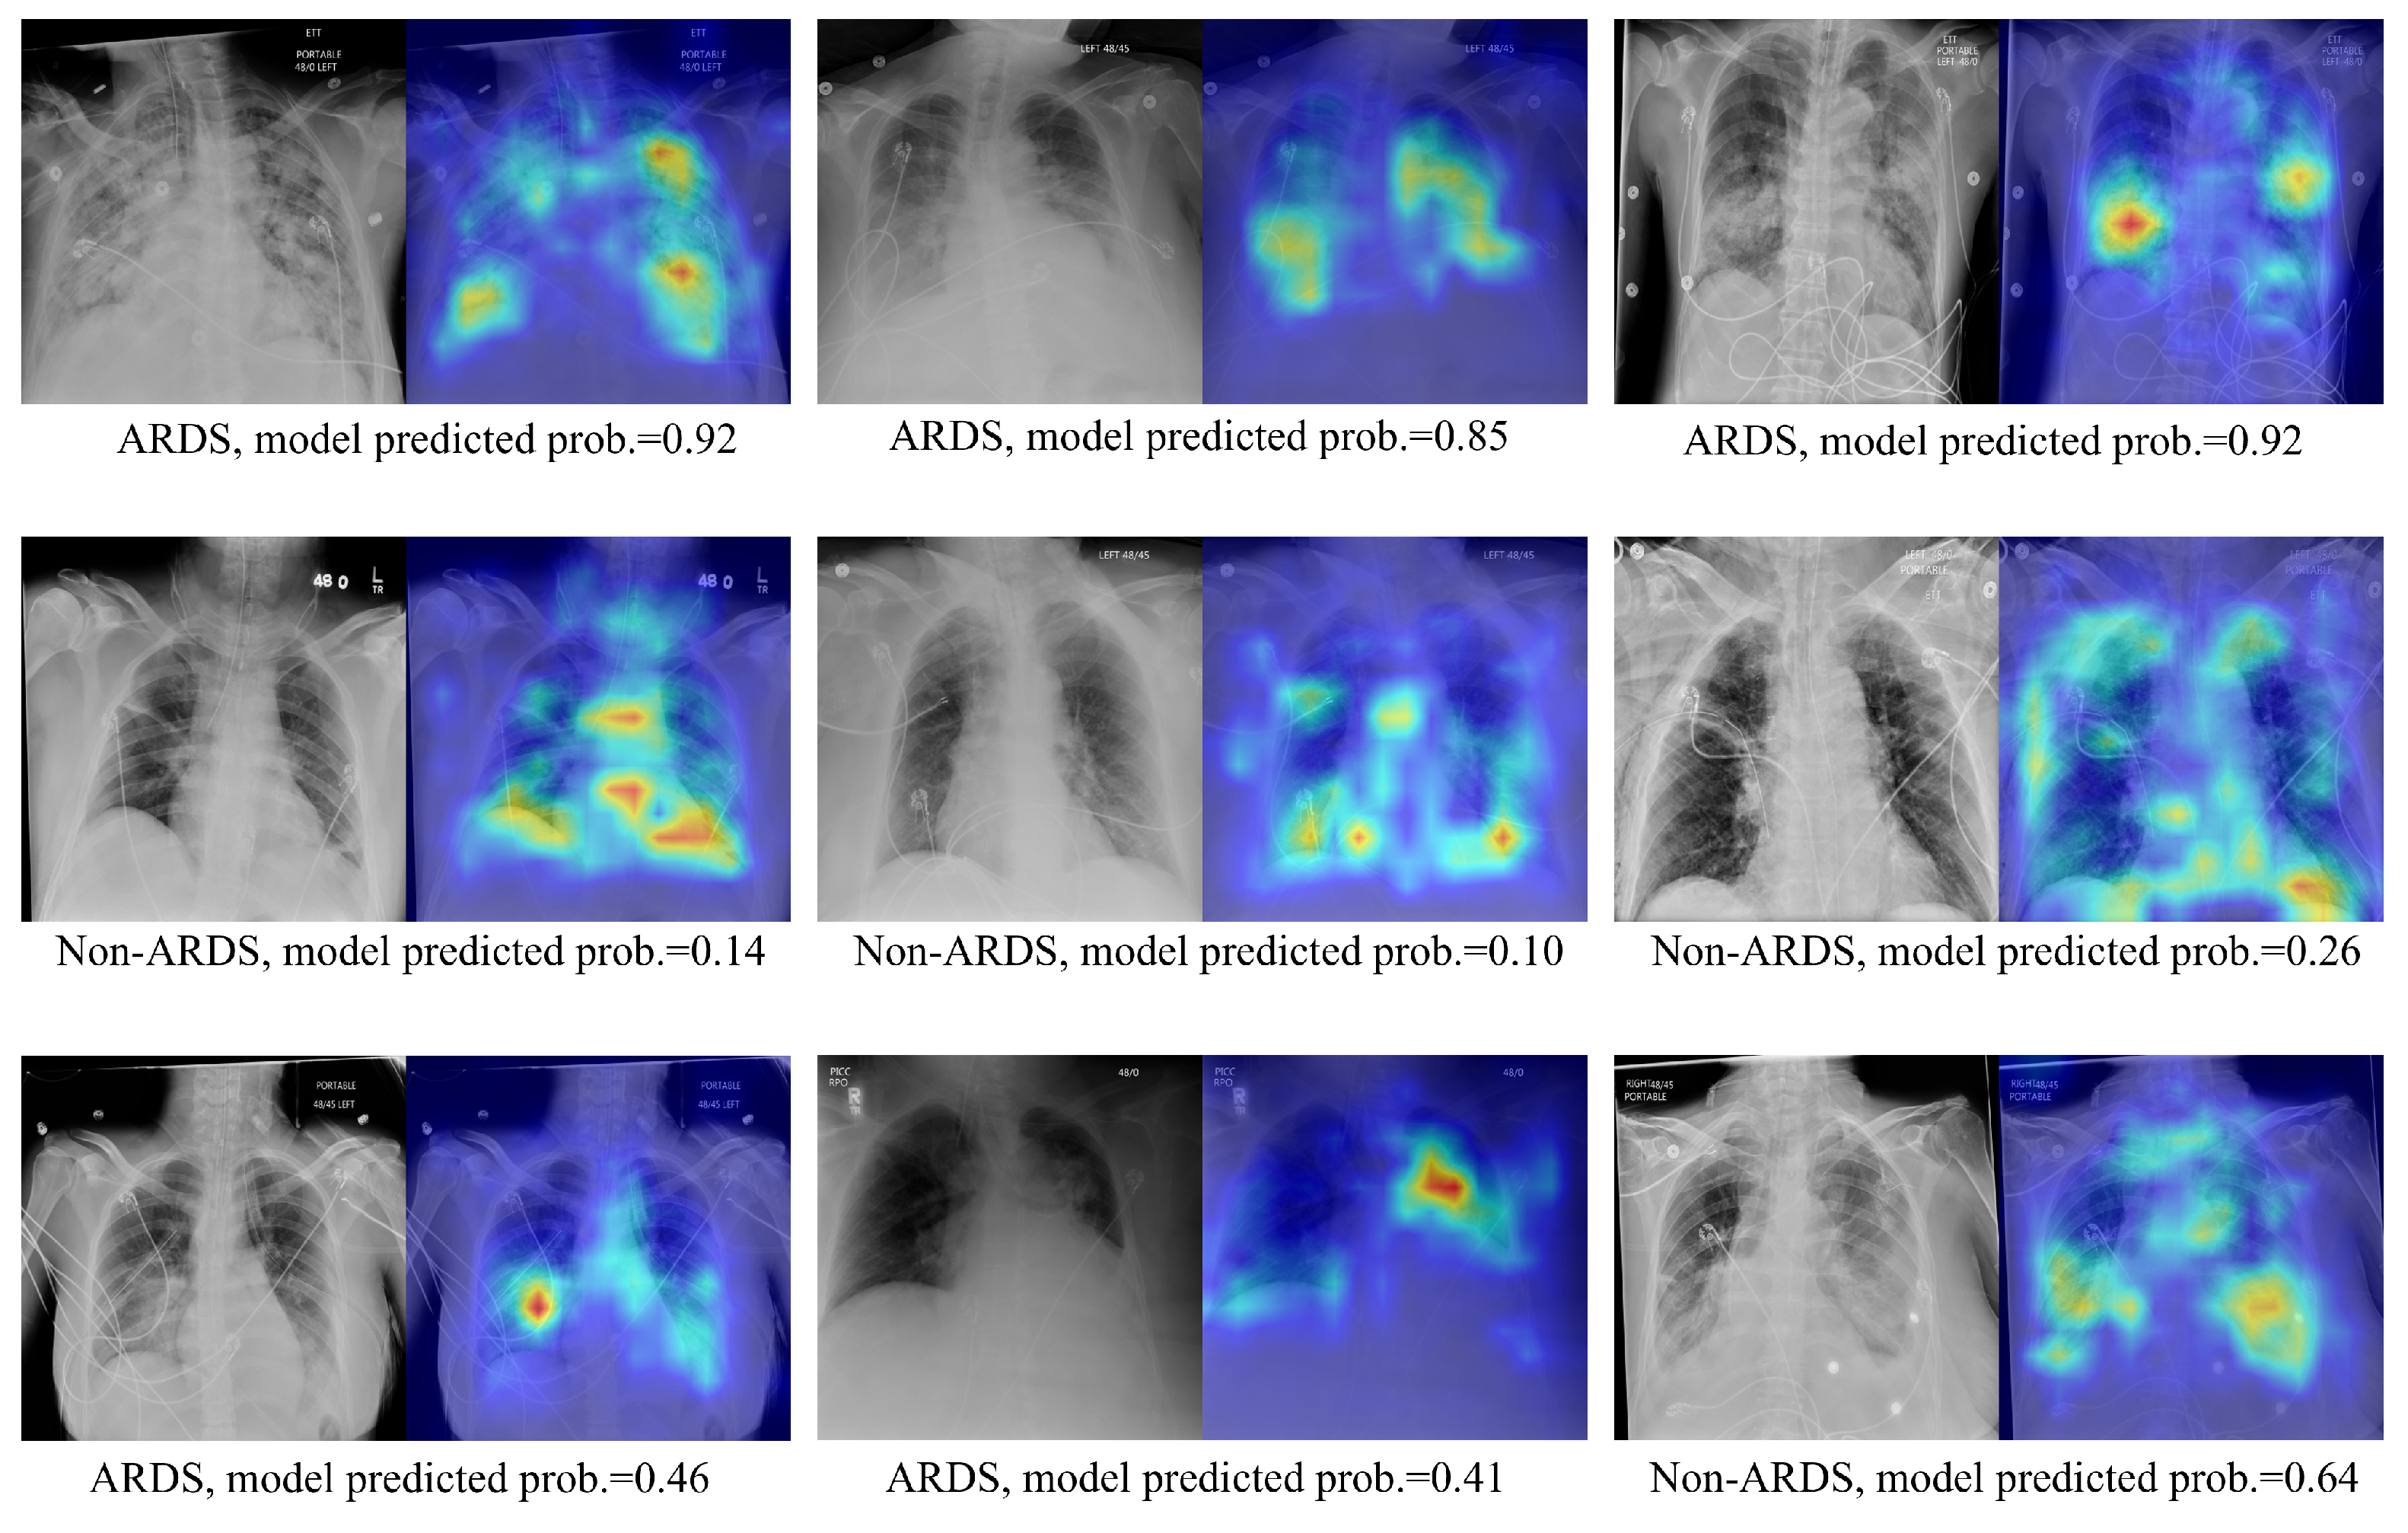

3.3. Qualitative Results Using the Score-CAM Approach on Test Images

Visualizations of the CXR images and their corresponding ScoreCAM heat maps from the proposed method are presented in Figure 5. The highlighted areas signify regions of interest during the model’s decision-making process for relevant classes. The upper panel exhibits the true positive cases, the middle panel displays true negative predictions, and the lower panel showcases highlighted regions when the model produces false positive or false negative predictions. In instances of true positive predictions, the areas of interest predominantly focus on lung regions that exhibit consolidations. True negative predictions see the model emphasizing the overall lung region and its corners. For incorrectly predicted cases, the model either concentrates on the region of interest but fails to make the correct prediction or is unable to highlight the correct region of interest. In addition, despite the existence of various medical devices, the model has not erroneously emphasized them in its predictions. This indicates the model’s robustness against confounding structures.

Figure 5.

Image pair featuring the original CXR alongside ScoreCAM heatmap-overlaid CXRs. The text below each image pair indicates the ground truth ARDS label and the probability of ARDS as predicted by the target model.